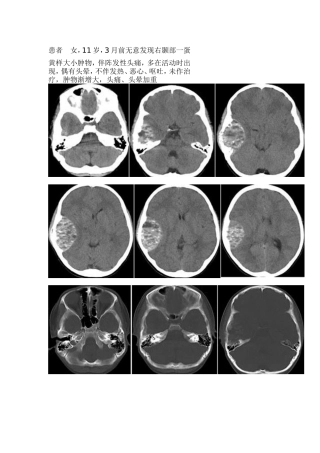

患者女,11岁,3月前无意发现右颞部一蛋黄样大小肿物,伴阵发性头痛,多在活动时出现,偶有头晕,不伴发热、恶心、呕吐,未作治疗,肿物渐...